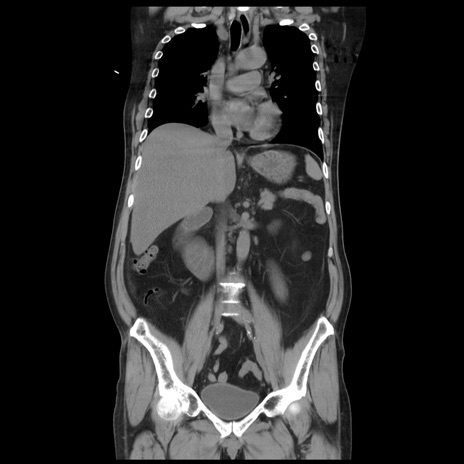

症例20(冠状断像)

【症例】 60歳代男性

【主訴】 腹部膨満、嘔吐

【現病歴】5日前頃より倦怠感を認め食事量減少し4日前の朝嘔吐、食事摂取困難となった。 3日前近医受診し点滴施行され整腸剤などを処方された。 当日他院を受診し、腹部膨満著明、炎症反応の上昇(CRP10.8、WBC11200)あり、紹介受診となる。

【身体所見】 意識JCS1 受け答えがはっきりしないBP 111/57mHg、 P 67bpm、、BT35.2°C、SpO2 97%(RA)、 腹部:膨隆、打診で鼓音あり、全体的に圧痛有り、腸蠕動音(-)、反跳痛ははっきりせず。

【データ】WBC 11400、CRP 14.20